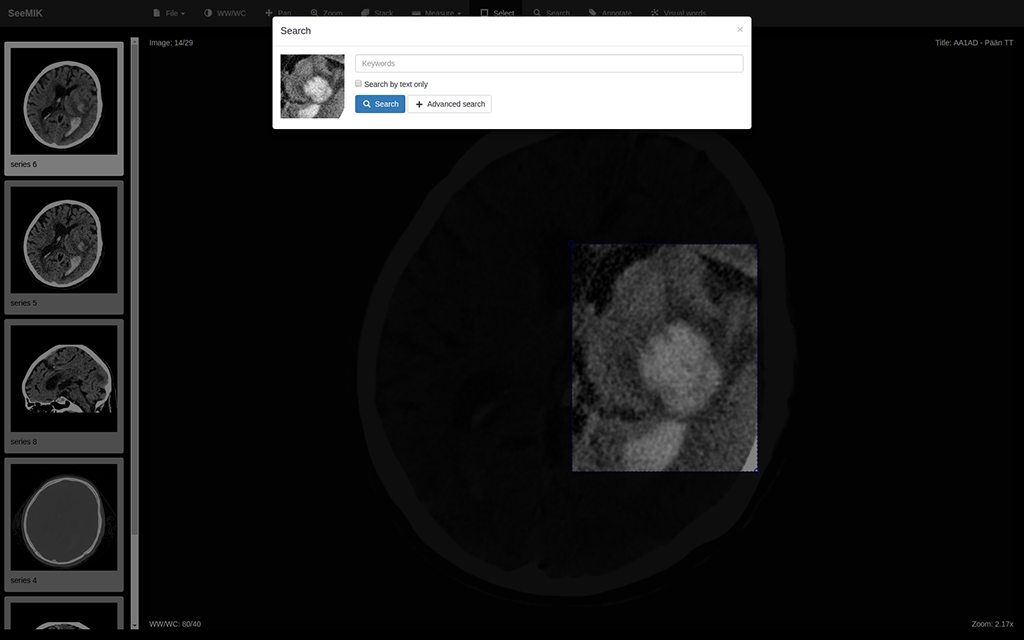

If radiologist is not sure which diagnosis better relates to existing findings, then he/she points out the feature of interest in the medical image and defines keywords.

• Data processing

SeeMIK finds keys for images with similar-appearing features and study reports related to keywords in index. It obtains by found keys real data from PACS and RIS and then shows it to radiologist.